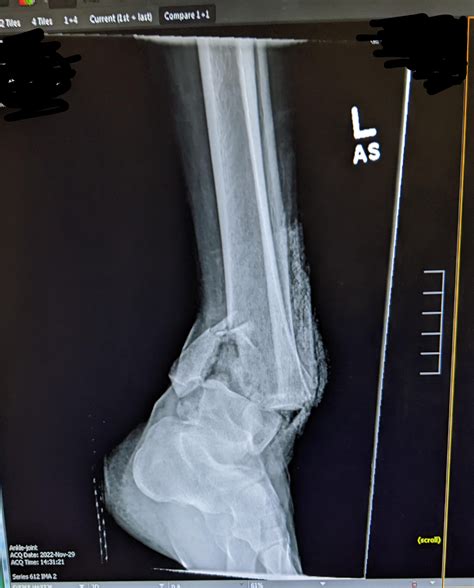

Diagnosing a Tib Fib Fracture involves a combination of physical examination and imaging tests. The diagnostic process typically includes:

• Physical Examination: A healthcare provider will assess the injured leg, checking for pain, swelling, and deformity.

• Imaging Tests: X-rays are the primary imaging tool used to confirm a Tib Fib Fracture. In some cases, additional tests such as CT scans or MRIs may be required for a more detailed view of the fracture.